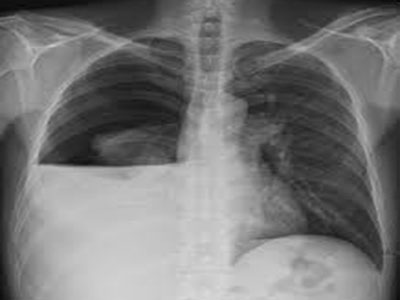

Los traumatismos del tórax son frecuentes en la actualidad (accidentes de tránsito, agresión, accidentes laborales) en sus diversas presentaciones, trauma torácico abierto y cerrado.

- Hemotórax

- Neumotórax

- Contusión pulmonar

- Fracturas costales